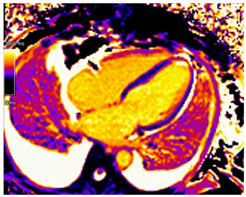

On CMR SSFP, better quantification of LV and papillary muscle mass can be made and tracked over time compared to echocardiography. Glycosphingolipid accumulation in myocytes results in a shorter T1 relaxation time on the T1 mapping sequence. In a systemic review, the mean T1 value in FD patients was 935 +/− 48 ms with a 1.5 T CMR scanner, compared to 999 + 31 ms in controls []. Shortened native T1 time has been described in individuals with FD without LVH and correlates with a reduced GLS on echocardiography []. Pseudo-normalization of native T1 time can be noted in areas of myocardial fibrosis or inflammation []. Native T2 mapping can show elevated T2 relaxation time in the basal inferolateral region or other areas of LGE, which reflects myocardial inflammation []. Post-contrast imaging would classically show a pattern of LGE involving the mid-myocardium of the basal inferolateral wall. However, LGE may become more extensive in advanced cases []. ECV values are normal in FD but may increase in areas of fibrosis. Key CMR findings in Fabry disease are summarized in Table 2.